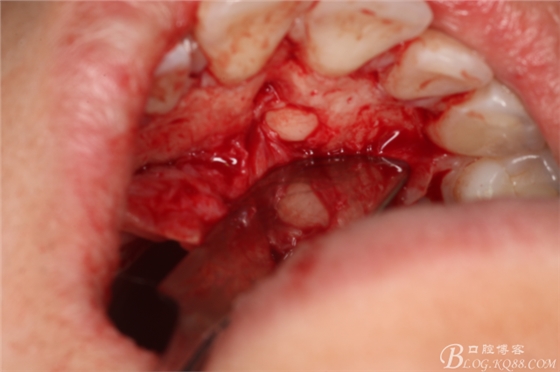

圖9.在切牙管旁邊去骨、暴露出21根尖區(qū)多生牙牙根

圖10.繼續(xù)去骨、發(fā)現(xiàn)多生牙部分位于鼻腭管內(nèi)